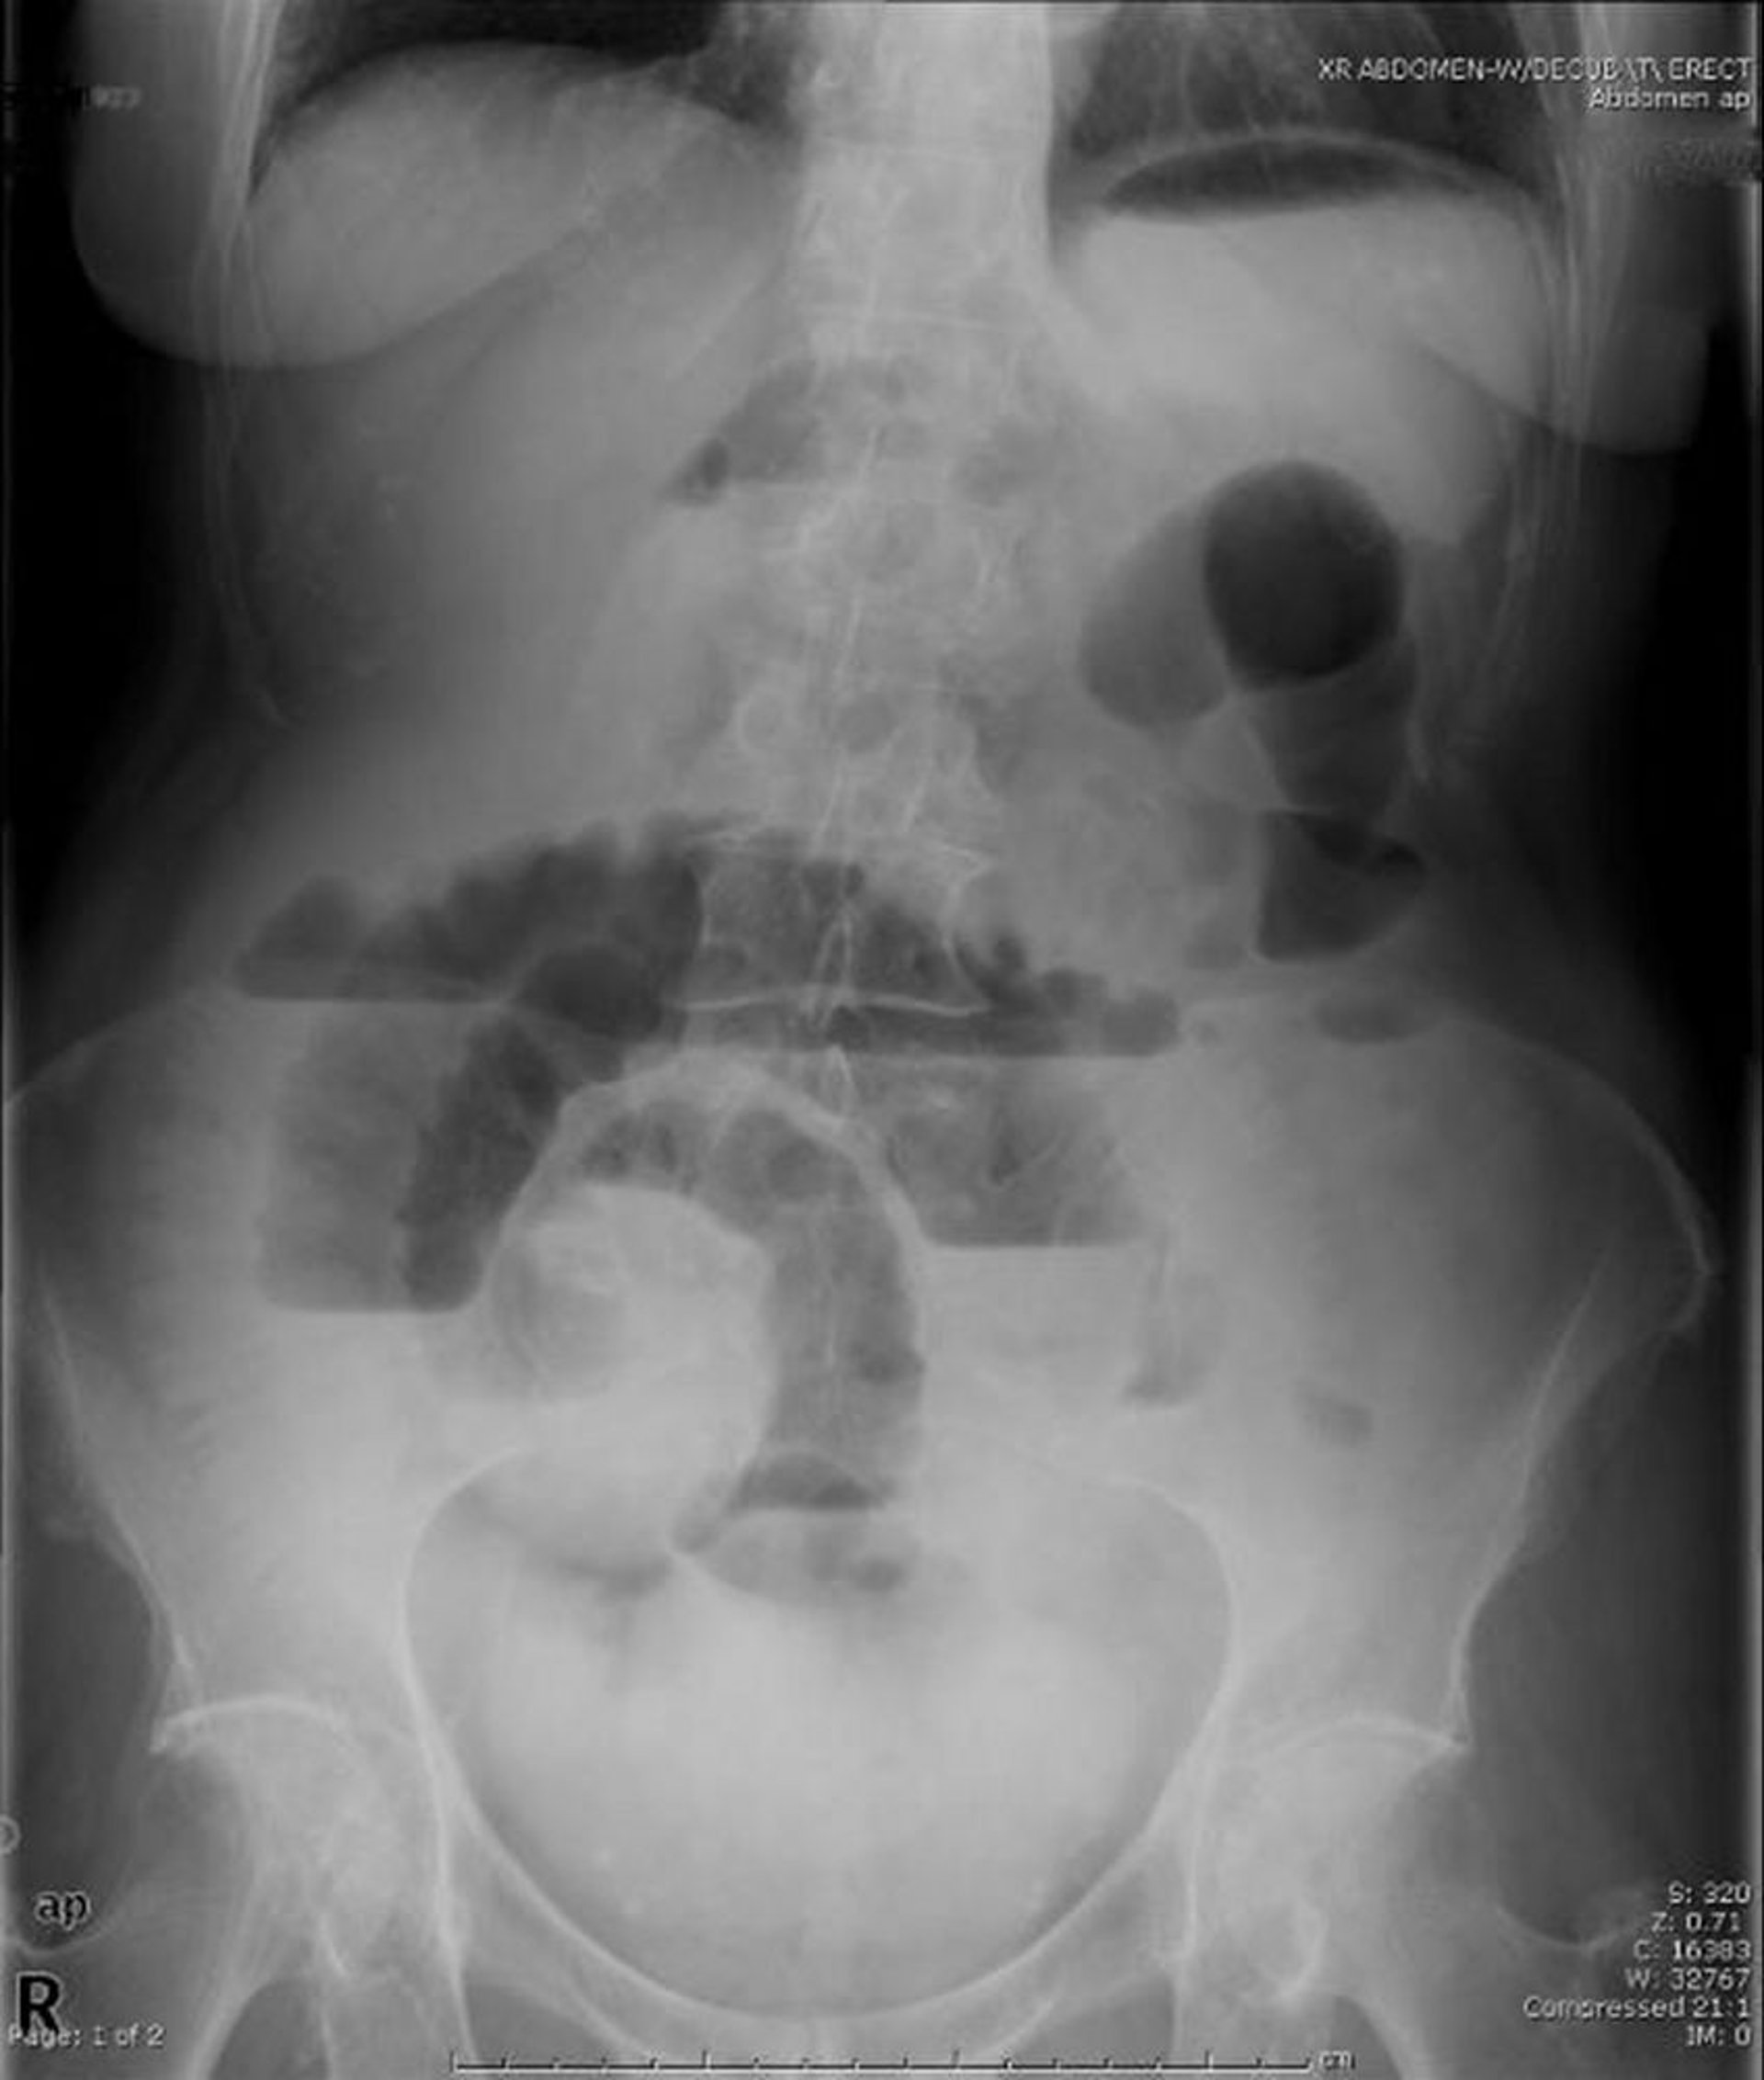

Occlusion de l'intestin grêle (radiographie debout)

Cette radiographie abdominale en position debout montre une obstruction de l'intestin grêle. Notez les multiples niveaux air-liquide.

Image provided by Parswa Ansari, MD.